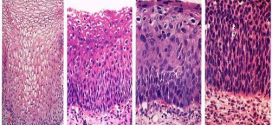

La neoplasia intraepitelial cervical (NIC, CIN). Los virus del papiloma humano (VPH) de los tipos 16 y 18 son los principales tipos que se asocian al cáncer ginecológico y genital. A saber, sin olvidar a los demás. Tumor maligno casi siempre y especialmente el formado por células epiteliales. Los canceres en grupos o categorías como el carcinoma, sarcoma, adenosarcoma, neoplasias, …